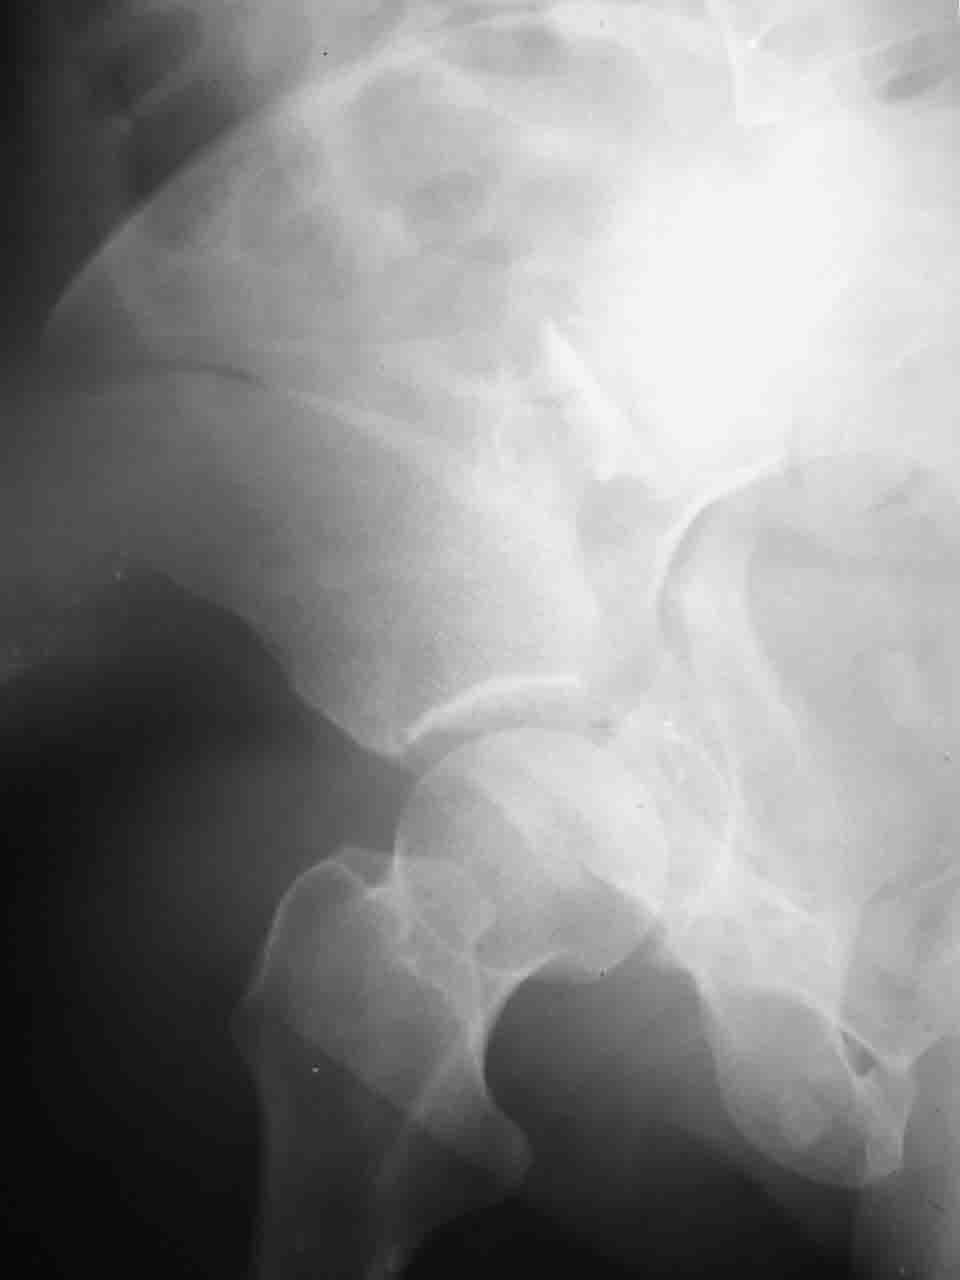

Причиной обращения к сообществу были возникшие непосредственно после операции сомнения и разочарования полученным качеством репозиции: а надо ли было трогать перелом вообще, репозиция передней колонны технически была очень сложна для меня, хотя реконструкции была в той же последовательности, что Д-р А.В.Рунков рекомендовал, в какой-то момент безуспешных манипуляций стал думать о *вторичной конгруэнтности*, которую не так давно обсуждали на

форуме и скелетном вытяжении. С репозицией и фиксацией задней колонны и отдельно задне-верхней стенки впадины проблем не возникло. Послеоп. Рг граммы в приложении. Если возникнут какие-либо дополнения или поправки - был бы признателен.

Вопрос доступа к вертлужной впадине при остеосинтезе задача не простая. Конечно, у Летурнеля и Тайла всё давно описано, нам остается только брать на вооружение. Но сами понимаете, что не бывает двух одинаковых ситуаций, поэтому в каждом случае вопрос решается сугубо индивидуально. Наша главная цель - восстановить анатомию с нанесением минимальной дополнительной травмы тазобедреннному суставу, думаю с этим никто не поспорит. Расширенный илиофеморальный доступ уж слишком травматичен (как сказал один коллега "таз лежит отдельно, больной отдельно").Стоит ли делать из пациента анатомический препарат для того чтобы легче ориентироваться. Да и нужно ли собирать всю "мозаику"? Мы применяли при таких операциях своеобразную операционную хитрость - сначала устраняли грубое смещение крыла под гребнем с фиксацией так называемой "плавающей" пластиной (временно фиксированной на двух винтах)- доступ или продлевали боковой, или делали небольшой дополнительный разрез над гребнем. Это позволяло устранить грубое смещение и захождение отломков тела повздошной кости, что значительно облегчало репозицию и остеосинтез впадины над сводом. Основное внимание конечно же уделяли нагружаемому задне-верхнему отделу. Сообщите ваш адрес, пришлю схемы и рентгенограммы.